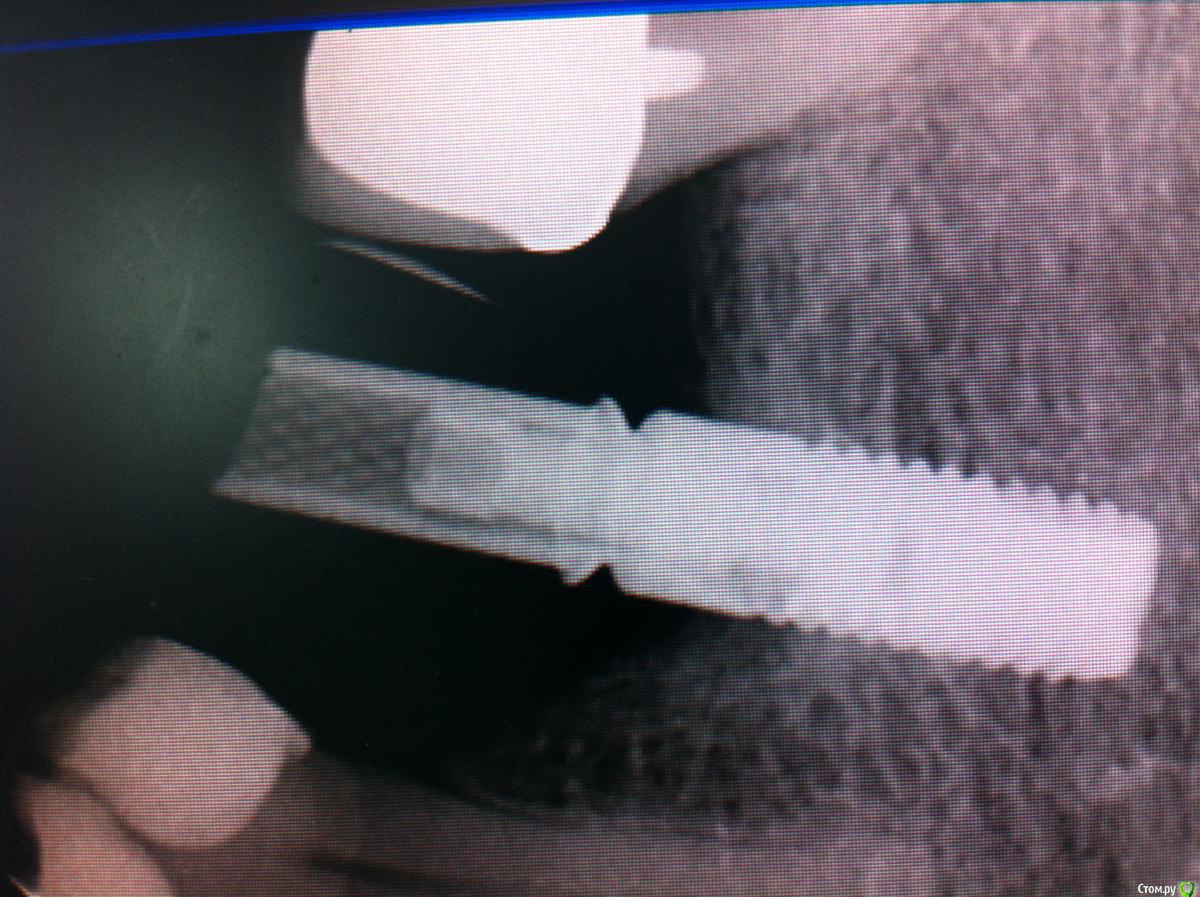

Айнур Фаязович Опубликовано 2 декабря, 2015 Поделиться Опубликовано 2 декабря, 2015 Пациентка обратилась с целью замены временной коронки на имплантате 36 на постоянную конструкцию. В ходе сбора анамнеза удалось выяснить, что 3 года назад у нее на 36 зубе произошла поломка винта внутри имплантата и, как следствие, появилась подвижность этой коронки. Ее доктору, у которого она протезировалась, удалось извлечь винт, но пришлось делать новую резьбу. Теперь она обратилась ко мне. Прилагаю фотографии полости рта, рентгеновские снимки до поломки винта, на момент обращения ( снимок с временной коронкой) и с трансфером для открытой ложки без винта (узкая платформа Астра). Дело в том, что у пациентки временная коронка на стандартном титановом абатменте ( платформа узкая 3,5-4,0) был зафиксирован с помощью винта от Dentium, при этом область шестигранника расширена изнутри ( чтобы проходил винт от Dentium) Но теперь возникают вопросы: 1)Как снять слепок с трансфером для узкой платформы, если родной винт не держится из-за изменения конфигурации резьбы, винт для широкой платформы и даже винт для Dentium слишком велики по размеру?2)Допустимо ли, по-вашему, менять конфигурацию постоянного абатмента в области шестигранника, расширяя его изнутри, чтобы проходил винт?3)Стоит ли проводить замену временной коронки на постоянную, если на рентгеновском снимке довольно серьезные повреждения в верхней части имплантата после изменения конфигурации резьбы. Уважаемые коллеги, если кто сталкивался с подобным, буду признателен за ваши варианты решений данной пробемы. За качество снимков прошу прощения, снимал на телефон. Ссылка на комментарий